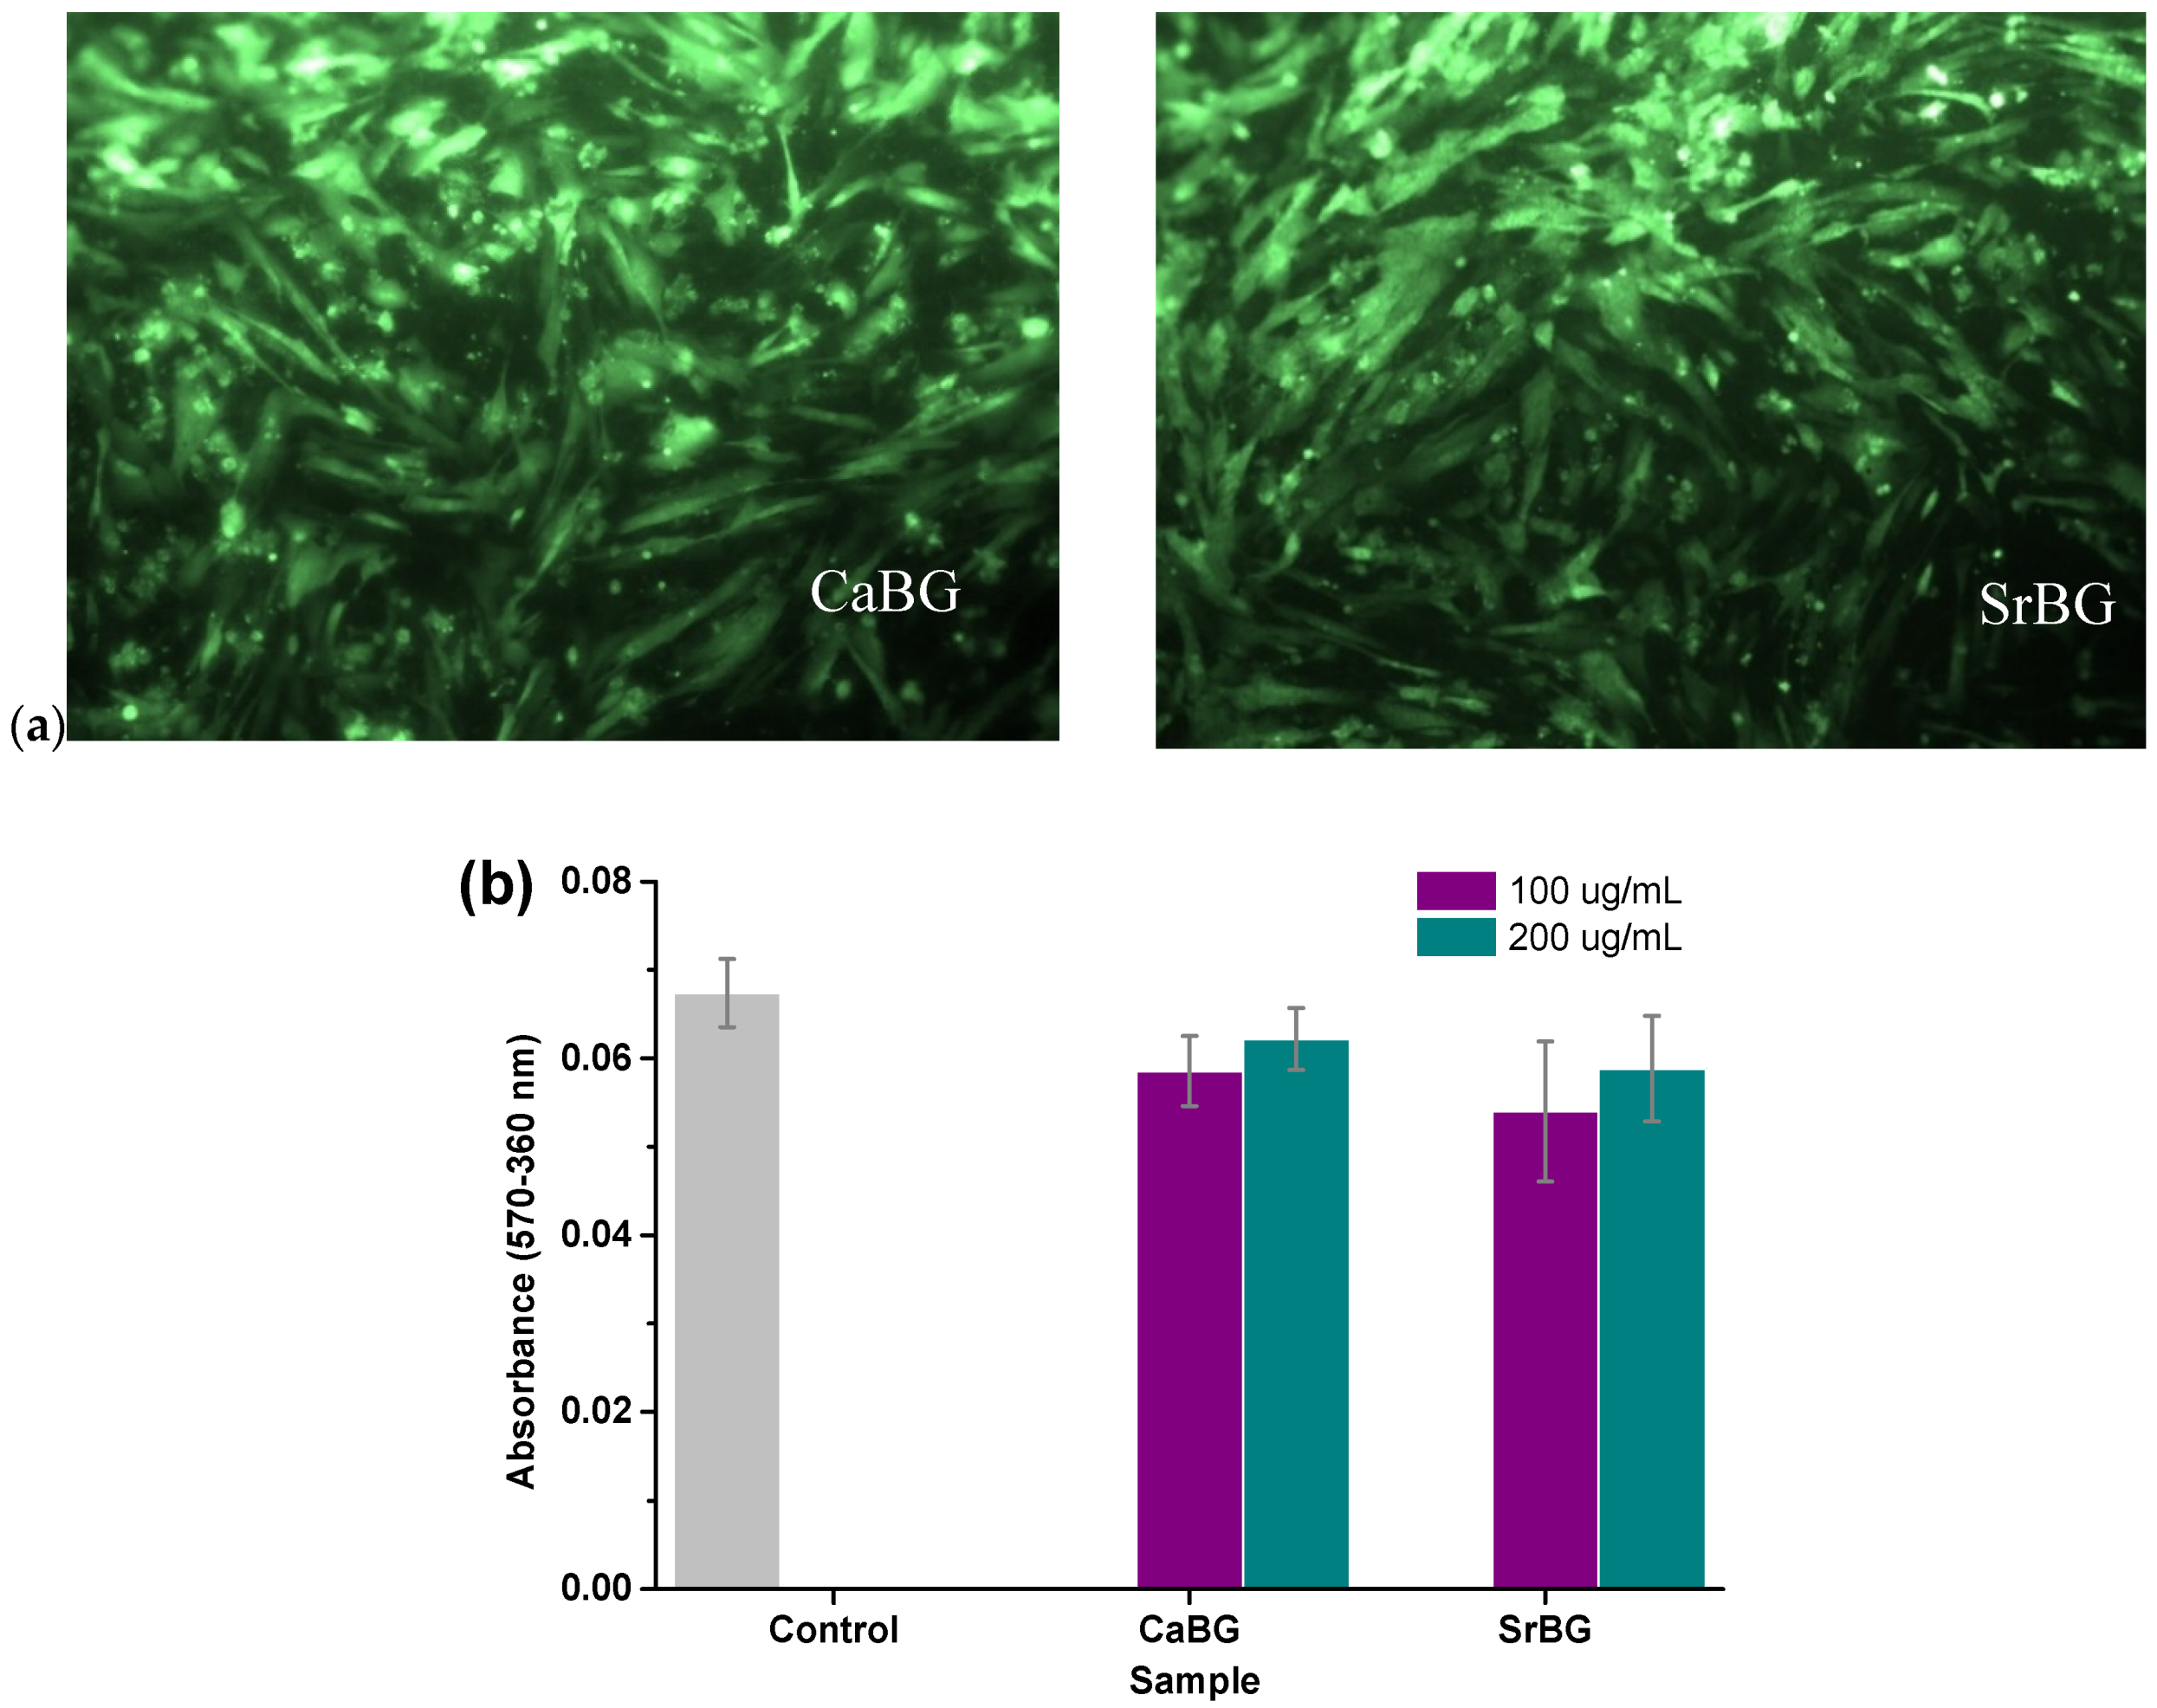

2.2.8. In Vitro Cytocompatibility and Osteogenic Potential